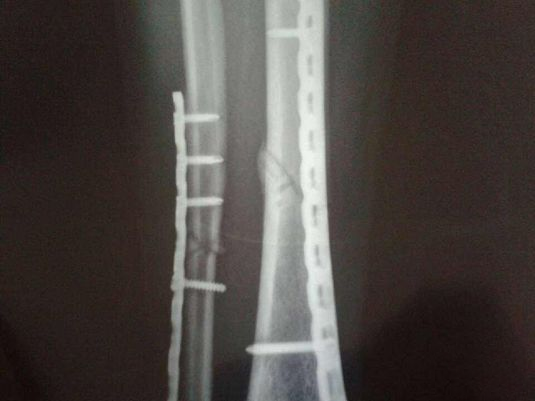

②手术治疗:分为切开复位内固定和支架外固定。适用于胫骨横形骨折、斜形骨折或螺旋形骨折.

钢板螺钉内固定

适用于各种类型的胫骨干骨折,尤以多段粉碎骨折效果好,但要求设备齐全。